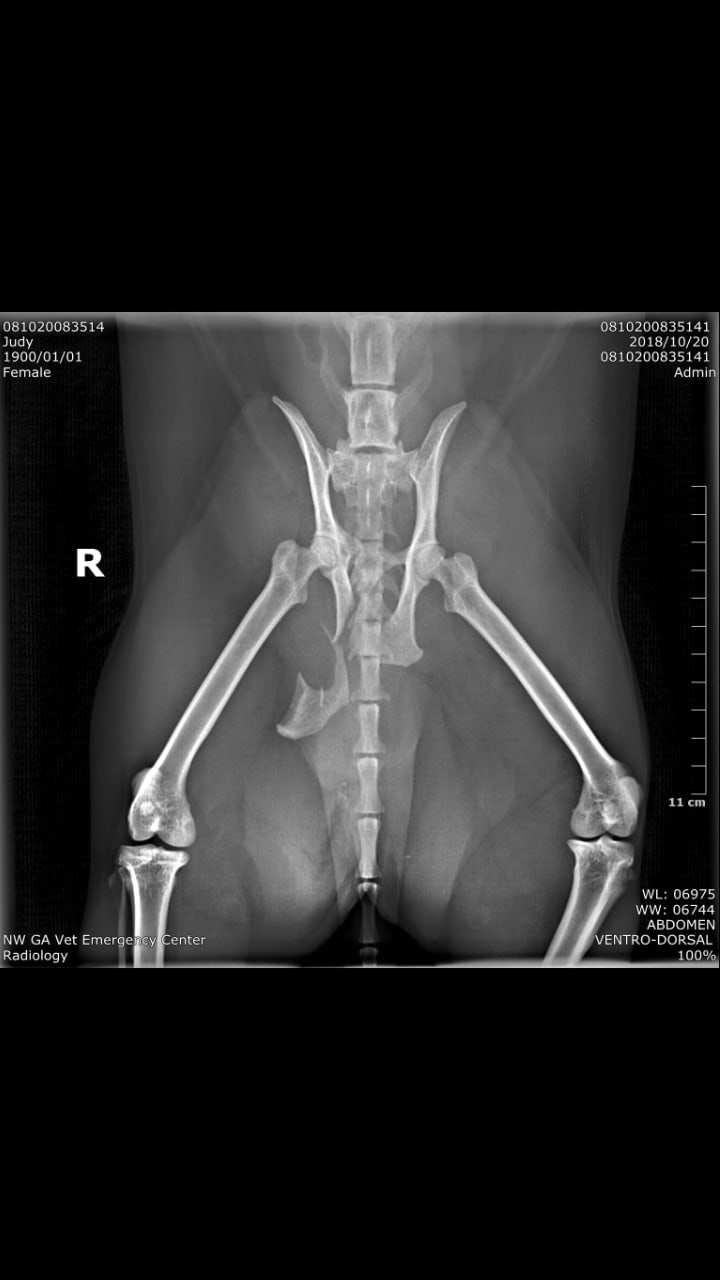

Cat broken pelvis: Is surgery recovery too painful, or should I put her down?

My cat broke her pelvis and we’re going to get her the surgery but our neighbor who was a vet tech said we would be helping her if we just put her down because the recovery from the surgery will be slow and painful what should I do

I don't find that to be the case at all. Most cats heal very well and quickly after surgery. Ultimately it is up to you on how you wish to proceed but I personally would do the surgery. Hope this helps. Best wishes.